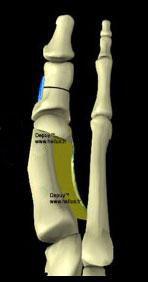

Puis, comme vous le voyez sur les schémas ci-contre, on sépare la tête du premier métatarsien de sa base avec une mini-scie oscillante. La tête de M1 est alors transférée vers le deuxième métatarsien pour réduire l'espace entre les deux premiers métatarsiens.

L'angle inter-métatarsien est corrigé par le transfert de la tête de M1 vers le deuxième métatarsien, fermant ainsi l'espace inter-métatarsien.

On peut y associer un abaissement ou un relèvement de la tête, une rotation pour réorienter la surface articulaire de M1 ou un allongement ou un raccourcissement.

Les pièces osseuses peuvent être fixées par vis en titane, le plus souvent canulées ou mieux sans ostéosynthèse, par enclavement osseux, évitant une éventuelle ablation secondaire, parfois difficile si la vis est enfouie sous l'os ou compte tenu de la multiplicité des empreintes de vis.